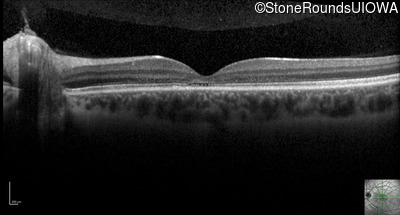

Optical Coherence Tomography - Right - 20/125 +1

Exemplar / OCT Stack